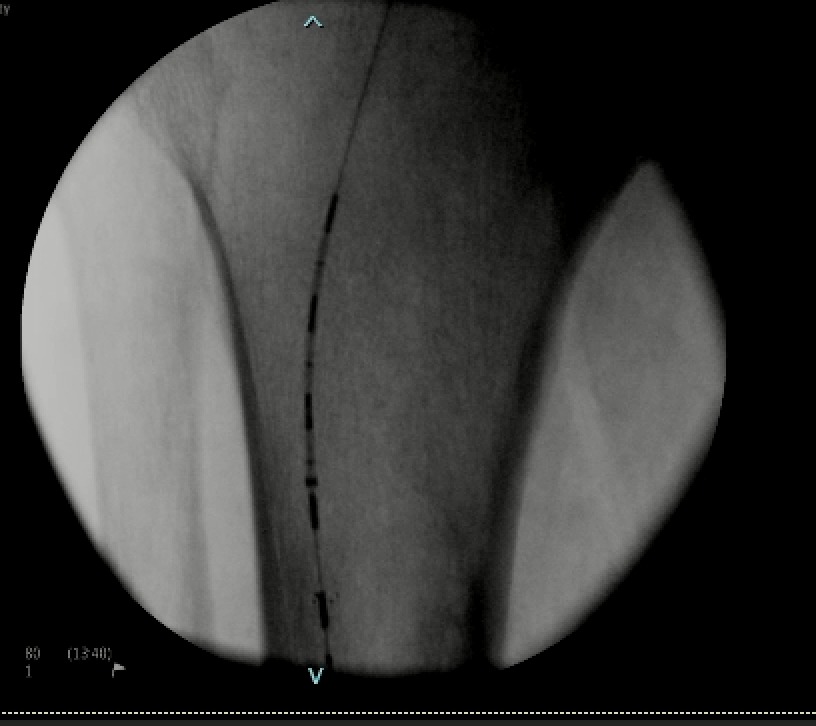

.@LucasRCmd, MPH; @HiroSparks, MD; Kara E. Masterson, MSN, NP; Scott J. Genshaft, MD; @AdamPlotnik, MD; and Siddharth A. Padia, MD, contributed to this open access article. See what they've been working on! brnw.ch/21wPx6v